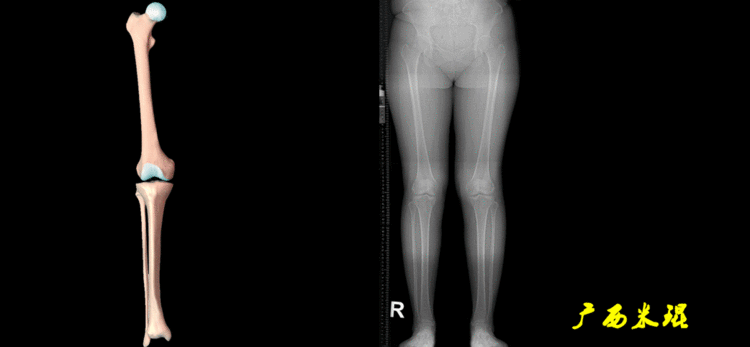

4、画出与机械轴相关的角度股骨近端外侧角(LPFA):沿股骨头中心与大粗隆最高点划一直线,连接股骨头中心与膝关节中心划一直线(机械轴),两者之间形成的外侧夹角,正常为90°±5°。

股骨远端外侧角(mLDFA):股骨内外侧髁远端切线(关节线)与股骨头和膝关节中心的连线(机械轴)两者之间形成的外侧夹角,正常为87°±3°。

胫骨近端内侧角(mMPTA):胫骨内外侧平台切线(关节线)与股骨头和膝关节中心的连线(机械轴)两者之间形成的内侧夹角,正常为87°±3°。

胫骨远端外侧角(mLDTA):胫骨远端切线(关节线)与下肢力线(机械轴)两者之间的外侧夹角,正常为89°±3°。

5、画出与解剖轴相关的角度解剖股胫角(aFTA):股骨干下段轴线(解剖轴)与胫骨上段轴线(解剖轴)在膝关节所形成的夹角,正常为174°±1°。膝关节OA的畸形常常由于一侧软组织及关节的过度磨损所致,临床多为内侧磨损过度,因此表现为轻度膝内翻畸形,X线表现为解剖股胫角小于174°,而胫骨角正常。

解剖股骨远端外侧角(aLDFA):股骨干下段轴线(解剖轴)与股骨内外侧髁远端切线(关节线)在膝关节外侧所形成的夹角,正常为81°±2°。大多数膝外翻患者的畸形发生于股骨下端,表现为股骨远端外侧角小于正常值。

解剖胫骨近端内侧角(aMPTA):胫骨内外侧平台切线(关节线)与胫骨解剖轴两者之间形成的内侧夹角,正常为87°±3°。由于胫骨解剖轴与机械轴几乎一致,所以一般解剖胫骨近端内侧角与机械胫骨近端内侧角一致。

解剖胫骨远端外侧角(aLDTA):胫骨远端切线(关节线)与胫骨解剖轴两者之间的外侧夹角,正常为89°±3°。由于胫骨解剖轴与机械轴几乎一致,所以一般解剖胫骨远端内侧角与机械胫骨远端内侧角一致。

解剖胫骨近端外侧角(也叫aMPTA):胫骨干上段轴线与胫骨平台切线(关节线)在膝关节外侧所形成的夹角,常称为胫骨角,正常为87°±3°。大多数膝内翻患者的畸形发生于胫骨上端,表现为胫骨角大于90°。严重的膝内翻畸形发生在整个下肢,股骨干及胫骨干都有可能形成向内弯曲的弧形。